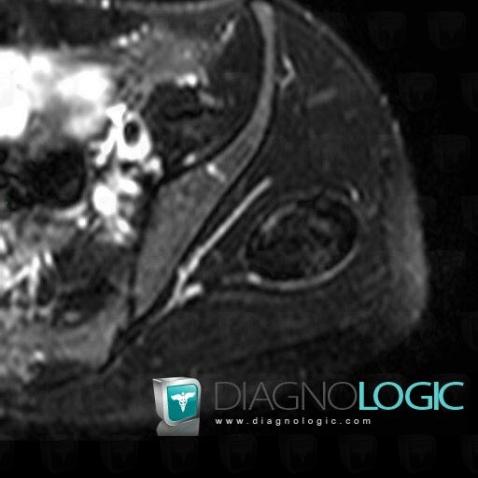

Hematoma, Pelvic Muscles, Other soft tissues/nerves - Pelvis, MRI

Here is the specific information in the key image above:

- Diagnosis Hematoma, Location(s) Pelvic Muscles, with gamuts T1 WI Hyperintense soft tissue lesionOther soft tissues/nerves - Pelvis, with gamuts T1 WI Hyperintense soft tissue lesion

- Diagnosis Hematoma, Location(s) Other soft tissues/nerves - Pelvis, with gamuts Hypointense T2 WI soft tissue lesionPelvic Muscles, with gamuts Hypointense T2 WI soft tissue lesion